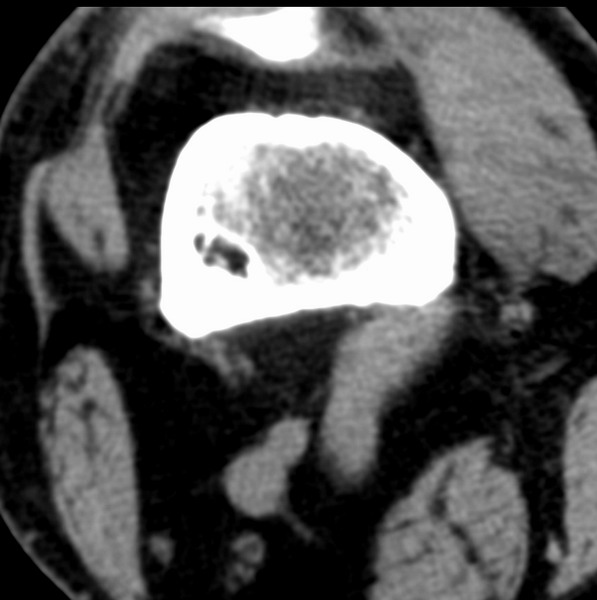

右侧膝关节疼痛一月

男、48

股骨下段、胫骨上段。

1、股骨干骺端病变考虑干骺端纤维性皮质缺损愈后(非骨化性纤维瘤)改变,胫骨近端内生骨瘤(或干骺端纤维性皮质缺损愈后改变);

2、骨关节炎,骨质增生,股骨外侧髁退变性囊肿(关节面软骨下囊肿);

股骨干骺端病变考虑干骺端纤维性皮质缺损愈后(非骨化性纤维瘤)改变,胫骨近端内生骨瘤(或干骺端纤维性皮质缺损愈后改变);

多发内生软骨瘤!

1、股骨干骺端病变考虑干骺端纤维性皮质缺损愈后(非骨化性纤维瘤)改变,胫骨近端内生骨瘤;

股骨干骺端病变考虑非骨化性纤维瘤。

支持非骨化性纤维瘤

非骨化性纤维瘤